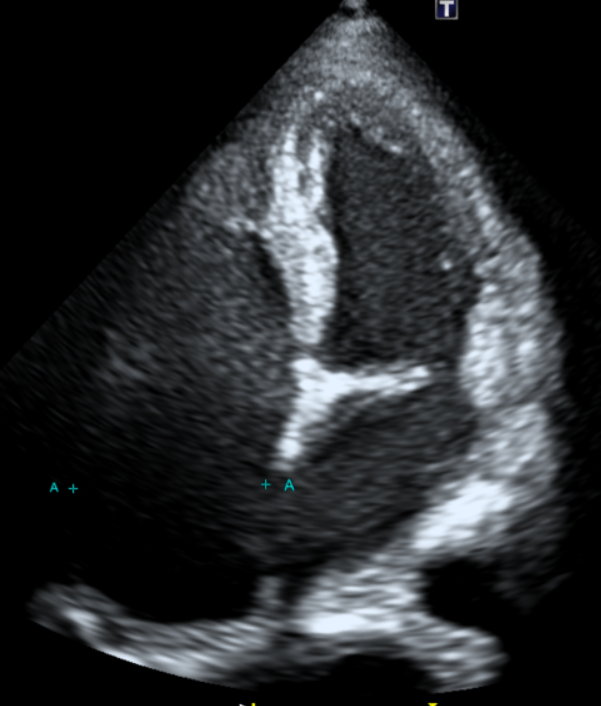

2. 심장초음파(도플러)

• Echo: 우심계 비대 Echo: 우심계 비대